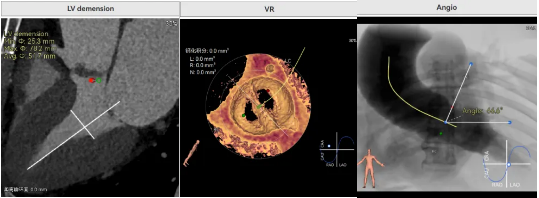

病例概览

患者病史 体检发现心脏瓣膜病半月余,平素无症状 ,有高血压病史。 后来院复查诊断为:主动脉瓣狭窄(重度)、先天性主动脉瓣二叶瓣畸形、心室肥厚、升主动脉扩张心功能 I 级(NYHA 分级)、高血压病 2 级(极高危)。 术前 CT:Type0型二叶瓣,瓣叶增厚,无钙化,类风湿性;瓣环径25.6mm,LVOT稍收窄,瓣环水平夹角66.6°,轻微横位心;左右冠开口高度可,瓣叶不长,无冠脉风险;心室收缩末内径约32mm,室壁增厚;外周入路无明显迂曲,无钙化、双侧内径可、双股中分叉,右侧为主入路能够支持20F大鞘通过。 造影角度及入路:LAO 6° CAU 13° 手术策略 采用右侧股动脉为主入路,左侧为辅助入路,常规穿刺。推荐使用20球囊预扩,预装TAV29瓣膜,初始定位对齐瓣环上0mm开始释放。 手术过程 20号球囊预扩无明显腰征 输送器过弓跨瓣顺滑 80%工作位观察 术后造影,瓣膜释放位置良好,无瓣周漏 术后超声:人工生物瓣释放后形态满意,瓣叶开放、关闭活动良好,无瓣周漏;跨瓣血流速度降至 2.5m/s,平均压力梯度6mmHg,符合手术预期。 Prostyle A®预装干瓣——“刚柔并济”助力临床最优化解决方案: 丝滑过弓能力:Prostyle A®短瓣架设计联合远端超滑亲水涂层,即使没有联合使用snare,都可以柔顺过弓,该例横位心的患者更好的展现了输送系统的柔顺性; 平衡的径向支撑力:该例患者Type0型二叶瓣,术后形态展开良好且无瓣周漏,在横位心等复杂情况下实现稳定锚定。 80%可回收设计:80%工作位观察,起搏时间更短,对患者损伤减少到最小,也利于术中精准调整瓣膜位置,保证术后效果。